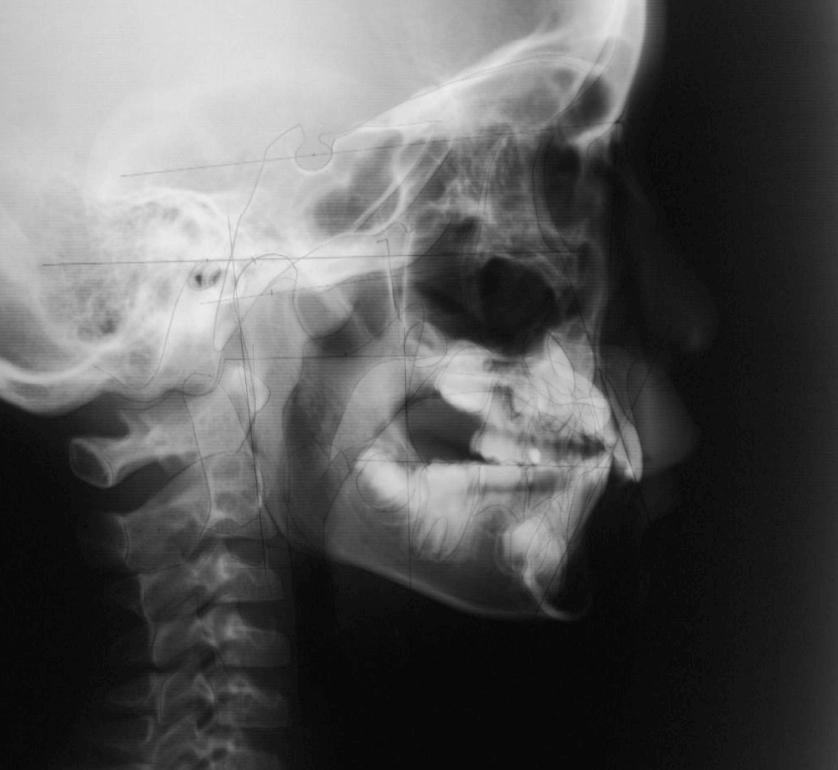

早期矯正治療 反対咬合症例①

主訴 | 前歯がうまく噛み合わず、食事時に違和感があるとのことで来院されました。保護者様からは、将来的な歯並びの不安についてもご相談がありました。 |

---|---|

診断結果 | 8歳7か月の男児 前歯の反対咬合(下顎前突)診断 |

治療内容 |

|

治療後の経過 | 動的治療は1年3か月で完了。反対咬合は改善されました。現在は3〜4か月ごとの定期検診で経過観察中で、今後本格的な矯正治療へ移行予定です。 |

治療期間 | 動的治療期間:1年3か月 治療回数:11回 |

治療費用 | 400,000円(税別) |